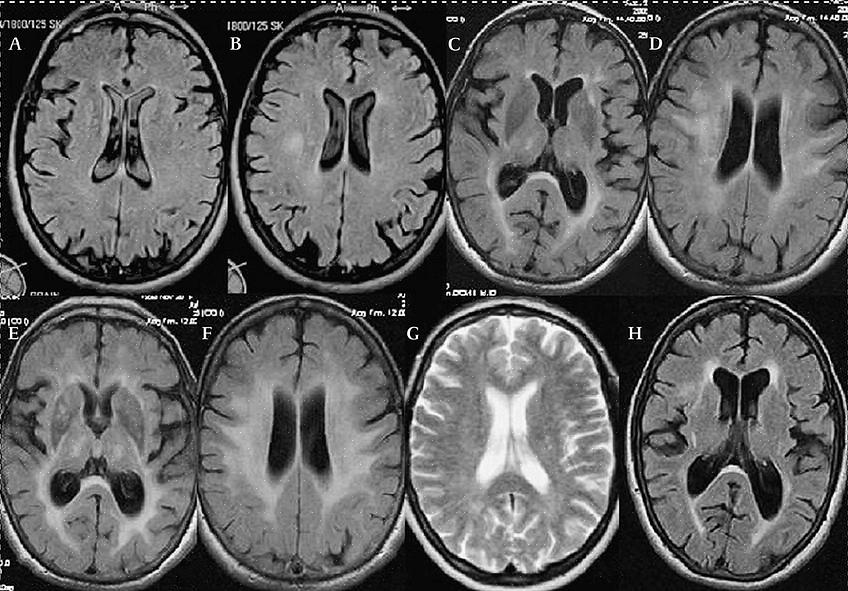

- ויטמין זה מייעל את תפקוד הנוירונים. אם יש לנו מחסור בוויטמין B12, יהיה לנו סיכון גבוה יותר לדמנציה, מה שמוביל לאלצהיימר (זכור, יש מתאם, אבל זה לא גורם ישיר).